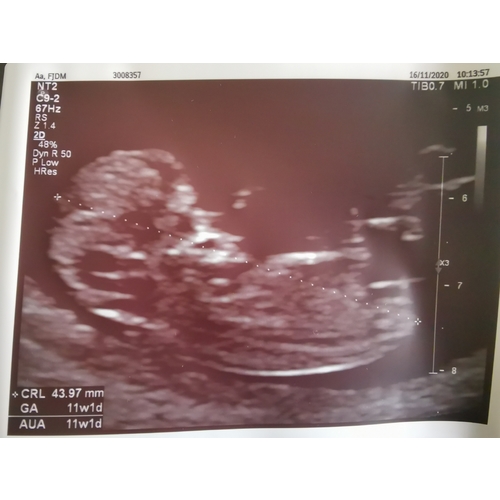

Vanmiddag de termijnen echo gehad, 19 oktober was ik 6 dagen terug gezet, vanmiddag bij de echo weer 6 dagen voorruit, de kleine deed het super, groeit goed en was een spring in het veld in de buik, heb een prachtig filmpje maar kan die niet plaatsen! Echt even een bevestiging van zwanger zijn! Ik heb 0.0 kwaaltjes dus maakte me toch wat zorgen dat het niet goed ging! Vandaag 11+4 wkn met de uitgerekende datum op 3 Juni 鉂も潳

Het is zo leuk!!! Geniet er lekker van! Zo鈥檔 bijzonder moment!! 馃槏 Het is nu echt een kindje met een neusje enzo wauw!

Ahh, mooie echo!!! Ik had ook vandaag nu 11+1馃挄